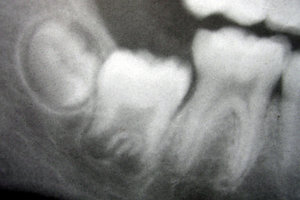

Regional odontodysplasia is rare, but is most likely to occur in the maxilla and anterior teeth. The cause is unknown; a number of causes have been postulated, including a disturbance in the neural crest cells, infection, radiation therapy, and a decrease in vascular supply (the most widely held hypothesis). Teeth affected by regional odontodysplasia never erupt into the mouth, have small crowns, are yellow-brown, and have irregular shapes. The appearance of these teeth in radiographs is translucent and "wispy," resulting in the nickname "ghost teeth".